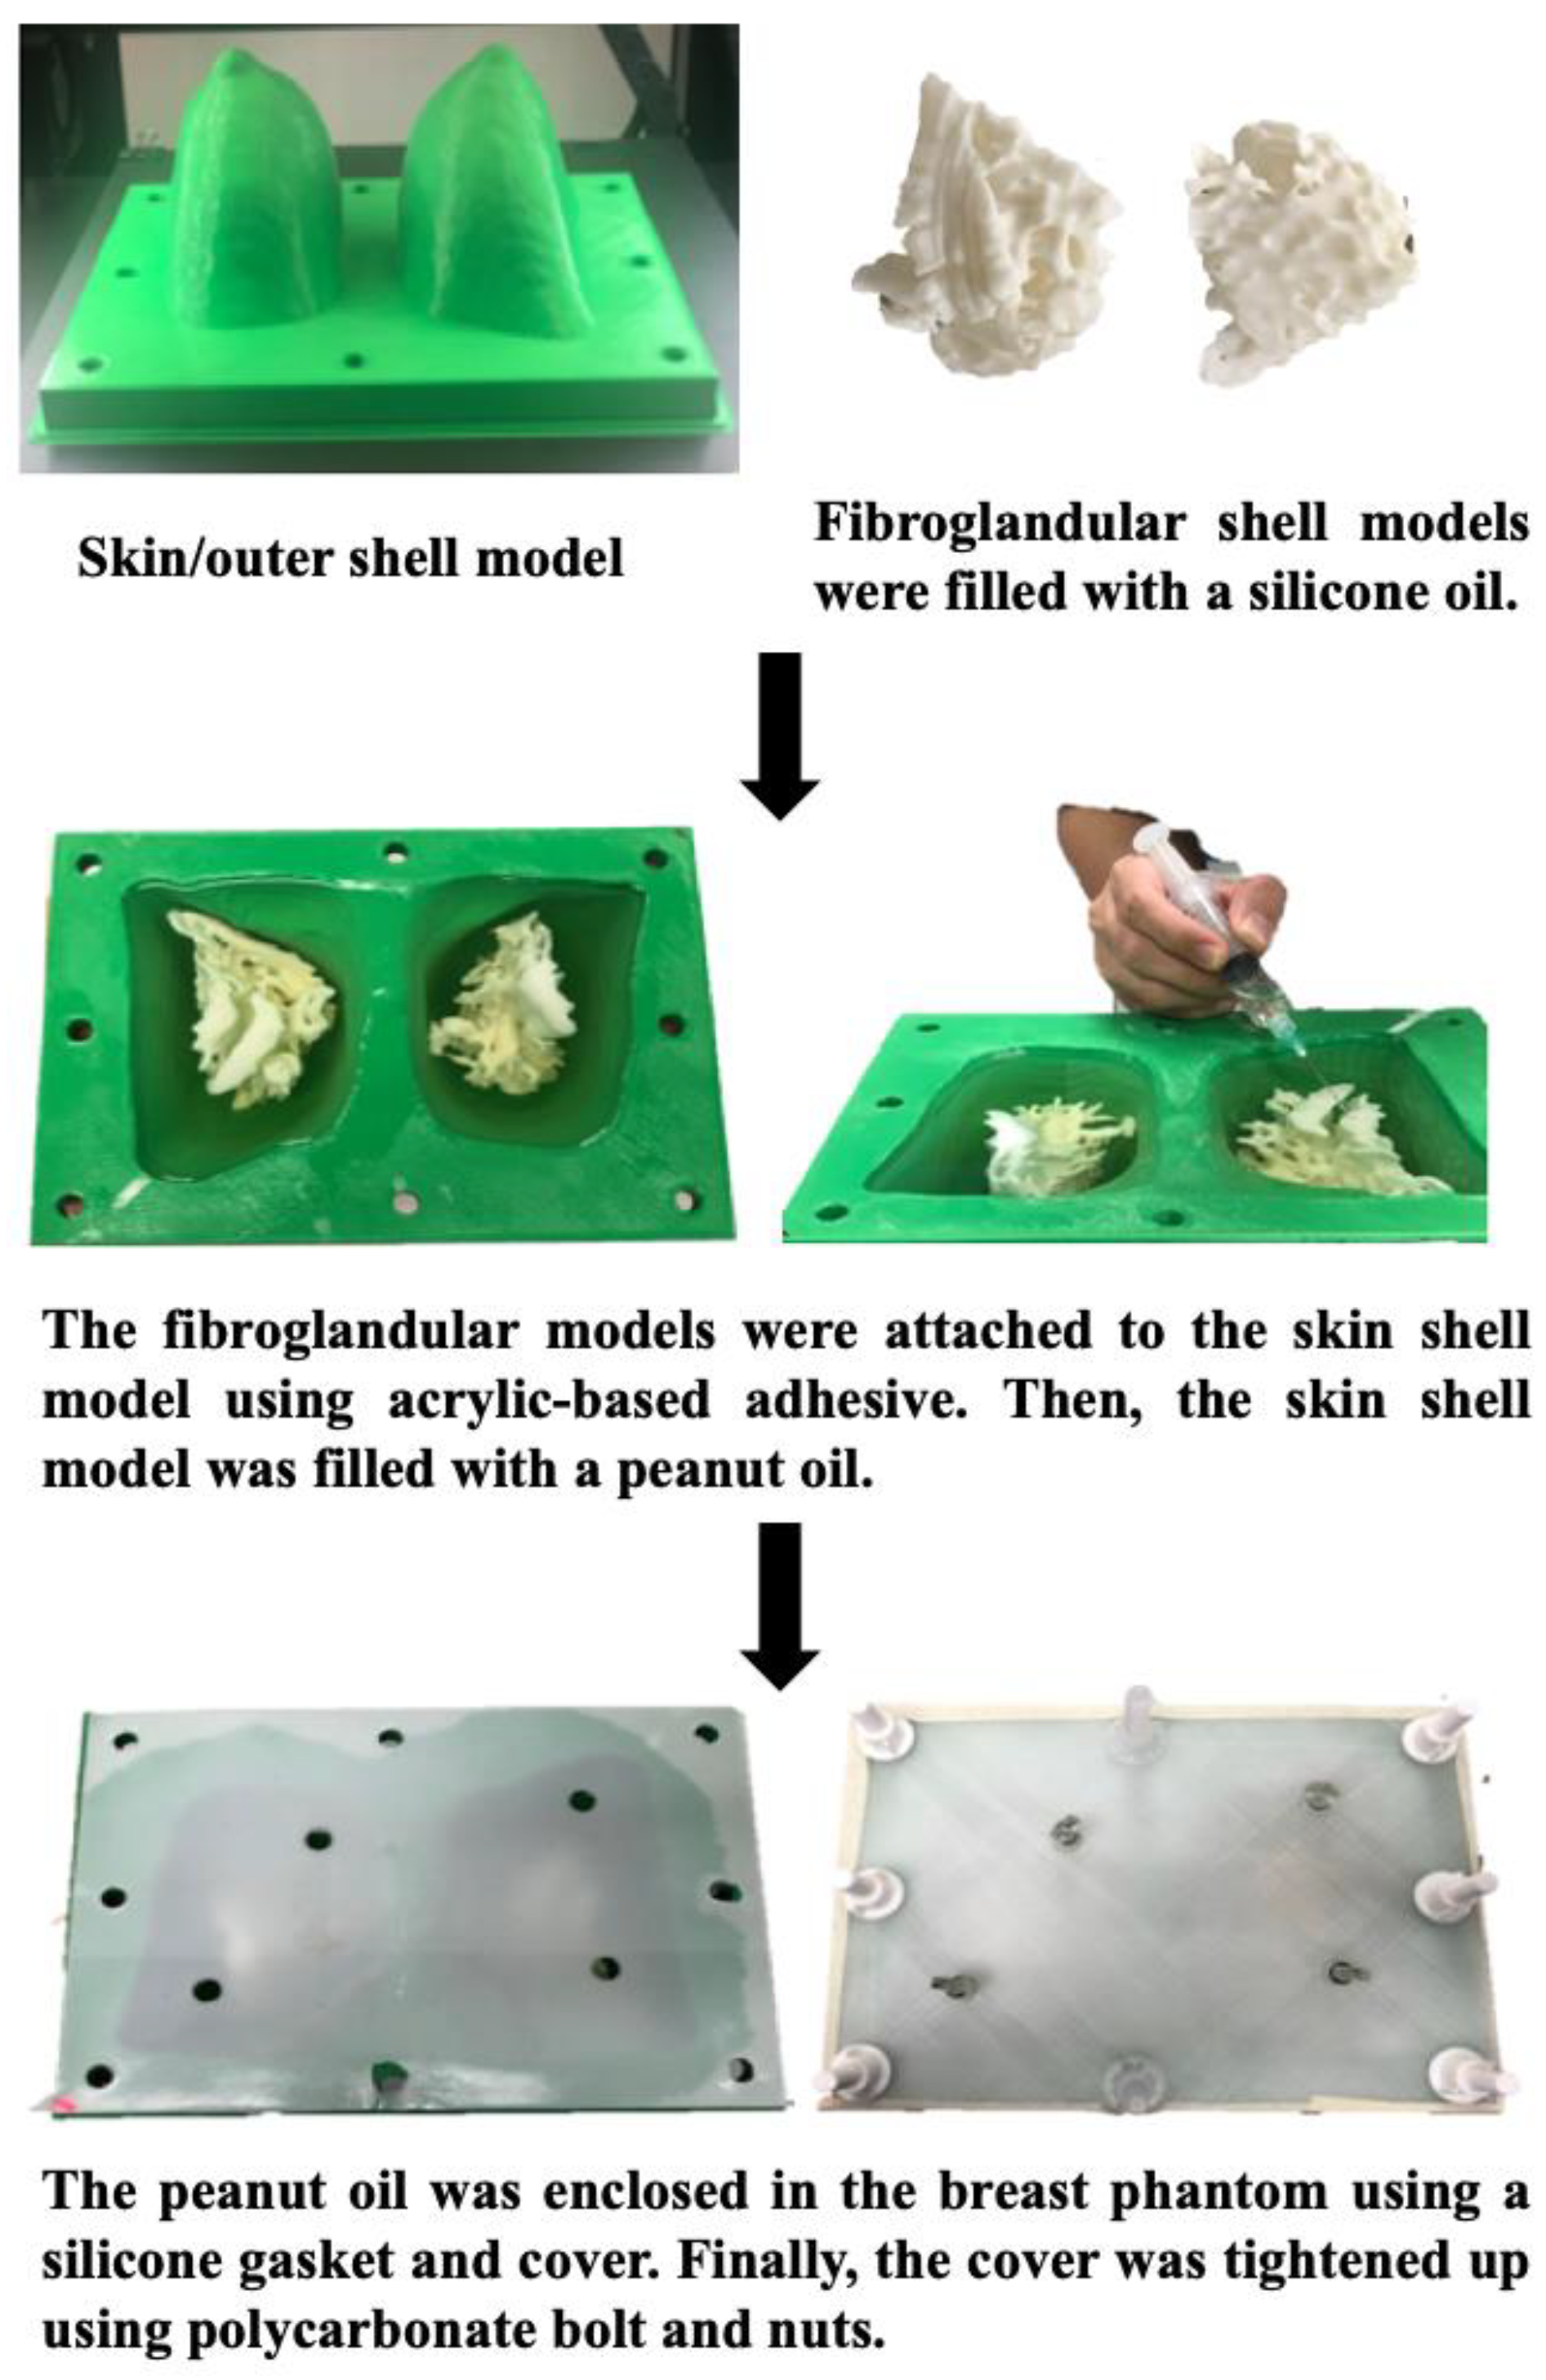

5.1. 3D-Printed Breast Cancer Model

- Sindi, R.; Wong, Y.H.; Yeong, C.H.; Sun, Z. Development of patient-specific 3D-printed breast phantom using silicone and peanut oils for magnetic resonance imaging. Quant. Imaging Med. Surg. 2020, 10, 1237–1248. [Google Scholar] [CrossRef]

- Sindi, R.; Wong, Y.H.; Yeong, C.H.; Sun, Z. Quantitative measurement of breast density using personalized 3D-printed breast model for magnetic resonance imaging. Diagnostics 2020, 10, 793. [Google Scholar] [CrossRef]

- He, Y.; Liu, Y.; Dyer, B.A.; Boone, J.M.; Liu, S.; Chen, T.; Zheng, F.; Zhu, Y.; Sun, Y.; Rong, Y.; et al. 3D printed breast phantom for multi-purpose and multi-modality imaging. Quant. Imaging Med. Surg. 2019, 9, 63–74. [Google Scholar] [CrossRef]

| Breast | 1 | MRI | Breast cancer model for breast MRI protocols | Printer: Breast skin shell was printed using Raise3D N2 Plus; Fibroglandular tissues were printed using Anycubic Photon S Materials: Breast skin shell was printed PLA; Fibroglandular tissues were printed using Magma H LINE Photopolymer Resin Cost: USD 30 for breast skin shell and USD 25 for fibroglandular tissues | Breast skin shell was printed at a resolution of 12.5 μm for the x and y-axis planes; 10 μm for z-axis plane Fibroglandular tissues were printed at a resolution of 47 μm for the x, y and z-axis planes Time: ~40 h for breast skin shell and 50 h for fibroglandular tissues |